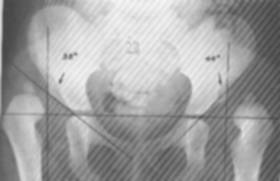

2. Displazia coxo-femurala

- este cea mai frecventa malformatie a aparatului locomotor, afectand cu predilectie sexul feminin (80%);

- examenul radiologic evidentiaza luxatia, forma si gradul ei de dezvoltare, factorii favorizanti si modificarile artrozice secundare; in acest sens au fost create o serie de puncte, linii si unghiuri de reper care vizeaza aprecierea procesului displazic de la nivelul bazinului, femurului si tulburarile raporturilor coxo-femurale;

- pentru aprecierea displaziilor de bazin se folosesc: unghiul de evazare a bazinului (verticala ce trece prin simfiza pubiana si o oblica pornita din unghiul inferior al pubelui la spina iliaca antero-superioara; normal are 500) si unghiul de sprijin al trunchiului pe membrele inferioare (oblica ce porneste de la unghiul inferior al pubelui la spina iliaca antero-superioara si axa colului femural; normal are 900)

- pentru aprecierea displaziilor de cotil se foloseste unghiul de acoperire a capului femural (perpendiculara in centrul capului femural si tangenta la marginea externa a cotilului; in displazia cu cotil insuficient este <150). Pentru aprecierea protruziei acetabulare se remarca marginea interna a capului femural care depaseste proiectia liniei nenumite, precum si unghiul de acoperire a capului femural care este>300.

- pentru aprecierea displaziilor colului femural se foloseste unghiul de inclinatie a colului (format de axa colului si cea metadiafizara, valoarea normala fiind de 124 -1300);

- pentru aprecierea raporturilor topografice coxo-femurale se folosesc si alte repere:

■cadranele Ombredane: orizontala care trece prin cartilajul in ‘’Y’’ si perpendiculara pe aceasta ce trece prin marginea externa a sprancenei cotiloide. La normali nucleul capului femural se afla in cadranul infero-intern.

■cadranul Putti: format din orizontale prin marginea inferioara a ‘’U’’-ului radiologic si cartilajul ‘’Y’’ si verticalele care trec prin marginea externa a sprancenei cotiloide si prin fundul acetabular. Normal, nucleul capului femural este situat in acest cadran.

■arcul cervico-obturator: constituit dintr-un arc continuu care indica contururile marginii superioare a gaurii obturate si inferioare a colului femural. In luxatii acest arc este intrerupt.

Fig.    114 - Cadranele Putti

Fig.    115 - Displazie coxofemurala

■linia Nelaton-Roser: uneste spina iliaca antero-superioara cu varful marelui trohanter (pe radiografiile laterale cu flexia coapsei pe bazin 450.